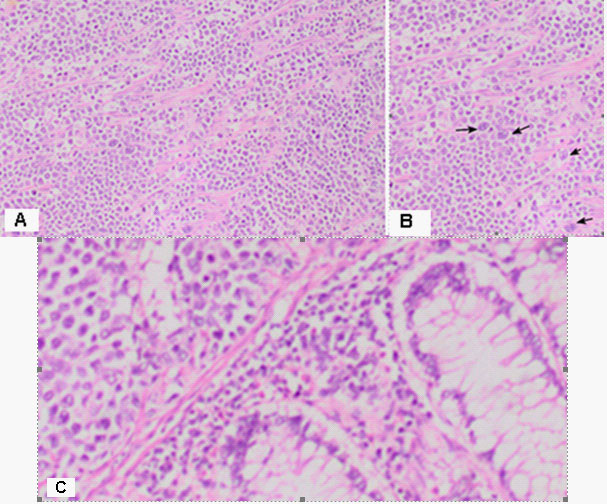

Figure 4: (A) The wall of colon with massive, diffuse infiltration from large and medium-sized neoplastic cells with slightly pronounced polymorphism, a dischositive way of growth, some of them with vesicular nuclei and prominent nucleoli H&E, x100. (B) In three of the surveyed seven lymph nodes, a diffuse deletion structure was established due to tumor infiltration H&E, x20.

DLBCL is neoplasm of large B lymphoid cells with nuclei at least 2× size of lymphocyte [20]. The pathomorphological characteristic is expressed by diffuse growth pattern with large cells (usually 5× normal lymphocytes) resembling immunoblasts (amphophilic cytoplasm, eccentric nuclei with one central nucleoli) or centroblasts (pale or basophilic cytoplasm, vesicular chromatin due to chromatin margination, 2 - 3 nucleoli, often near membrane), or rarely, anaplastic, associated with neutrophils [21]. In Figure 3 we present diffuse tumor cells with scarce cytoplasm, circular polymorphic nuclei with visible nucleoli and high mitotic activity / over 10 mitoses per 10 high-power fields. In Figure 4A is clearly seen the wall of colon with massive, diffuse infiltration from large and medium-sized neoplastic cells with slightly pronounced polymorphism, a dischositive way of growth, some of them with vesicular nuclei and prominent nucleoli. In three of the surveyed seven lymph nodes, a diffuse deletion structure was established due to tumor infiltration (Figure 4B).